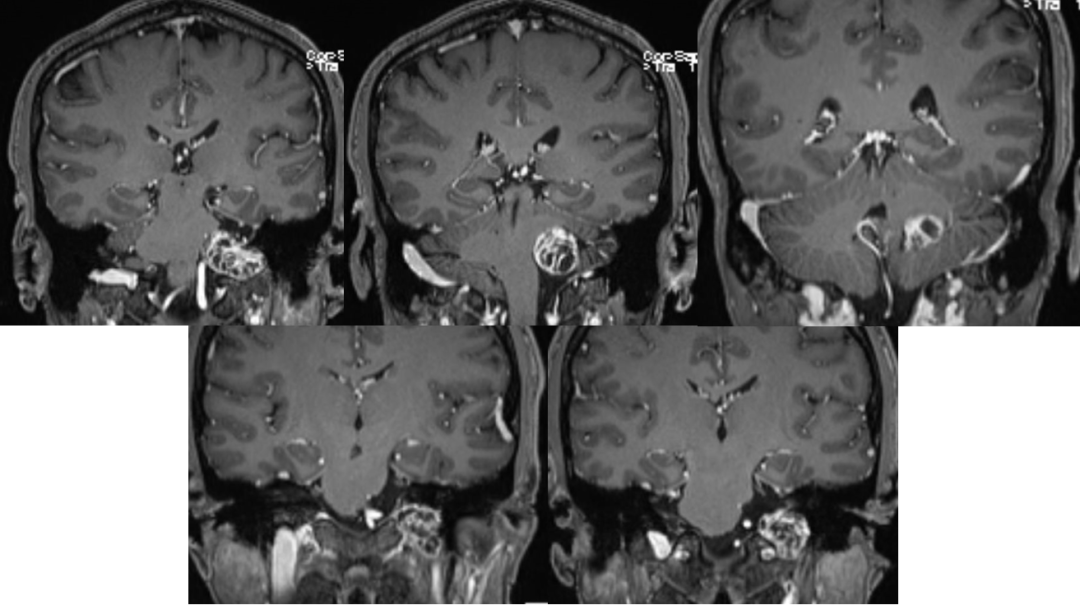

术前影像

![]()